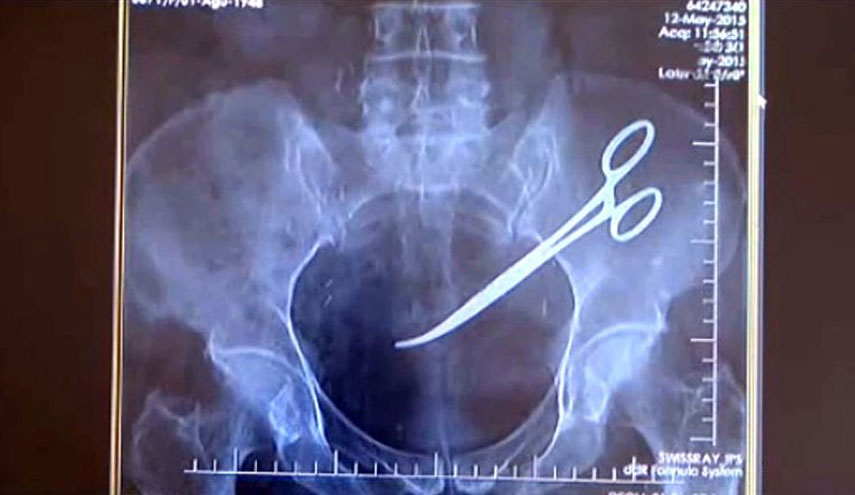

العراق-الكوثر: كشف مصدر طبي في محافظة أربيل شمال العراق، الاربعاء، انه تم إخراج مقص طبي من داخل إمعاء أحد المرضى بعد 34 سنة من إجرائه عملية للمعدة.

وقال المصدر، إن "فريقا طبيا تمكن من إخراج مقص للعمليات الطبية من داخل إمعاء احد المرضى في مستشفى زركاري بأربيل"، مبينا أن "المريض اجرى في عام 1984 عملية للمعدة ونسى الاطباء المقص داخل معدته في حينها، دون أن يشعر بالالم طيلة تلك الفترة".

وأضاف المصدر الذي طلب عدم الكشف عن اسمه، أن "الاطباء اكتشفوا بوجود المقص بعدما تعرض المريض لحالة طارئة"، موضحا أن "الفريق الطبي تمكن من إخراج المقص بعملية ناجحة".